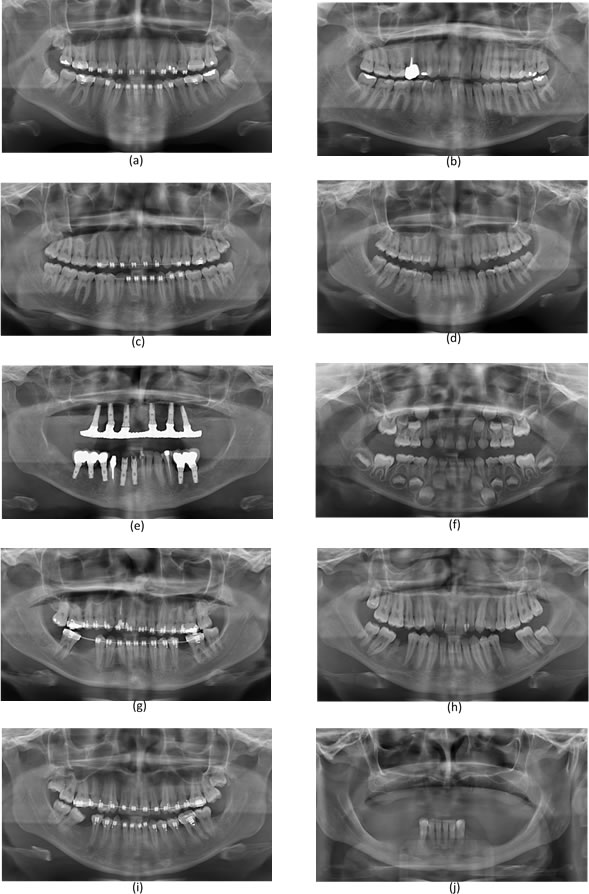

To thoroughly benchmark the methods studied here, the 1,500 images were distributed among 10 categories. The images were named, using whole numbers, in sequential order by category, aiming at not identifying the patients in the study. The process of categorizing the images was performed manually, selecting images individually, counting tooth by tooth, as well as verifying structural characteristics of the teeth. The images were classified according to the variety of structural characteristics of the teeth (see Table 5). Finally, the images were cut out to disregard non-relevant information (white border around the images and part of the spine) generated by the orthopantomograph device. After the clipping process, there was a change in the size of the images to 1991 1127 pixels, but without affecting the objects of interest (teeth), as shown in Figure 2. The cropped images were saved on the new dimension to be used in the following stages, which will be presented in the next sections. Figure 3 shows an X-ray image corresponding to each of the categories of our data set.